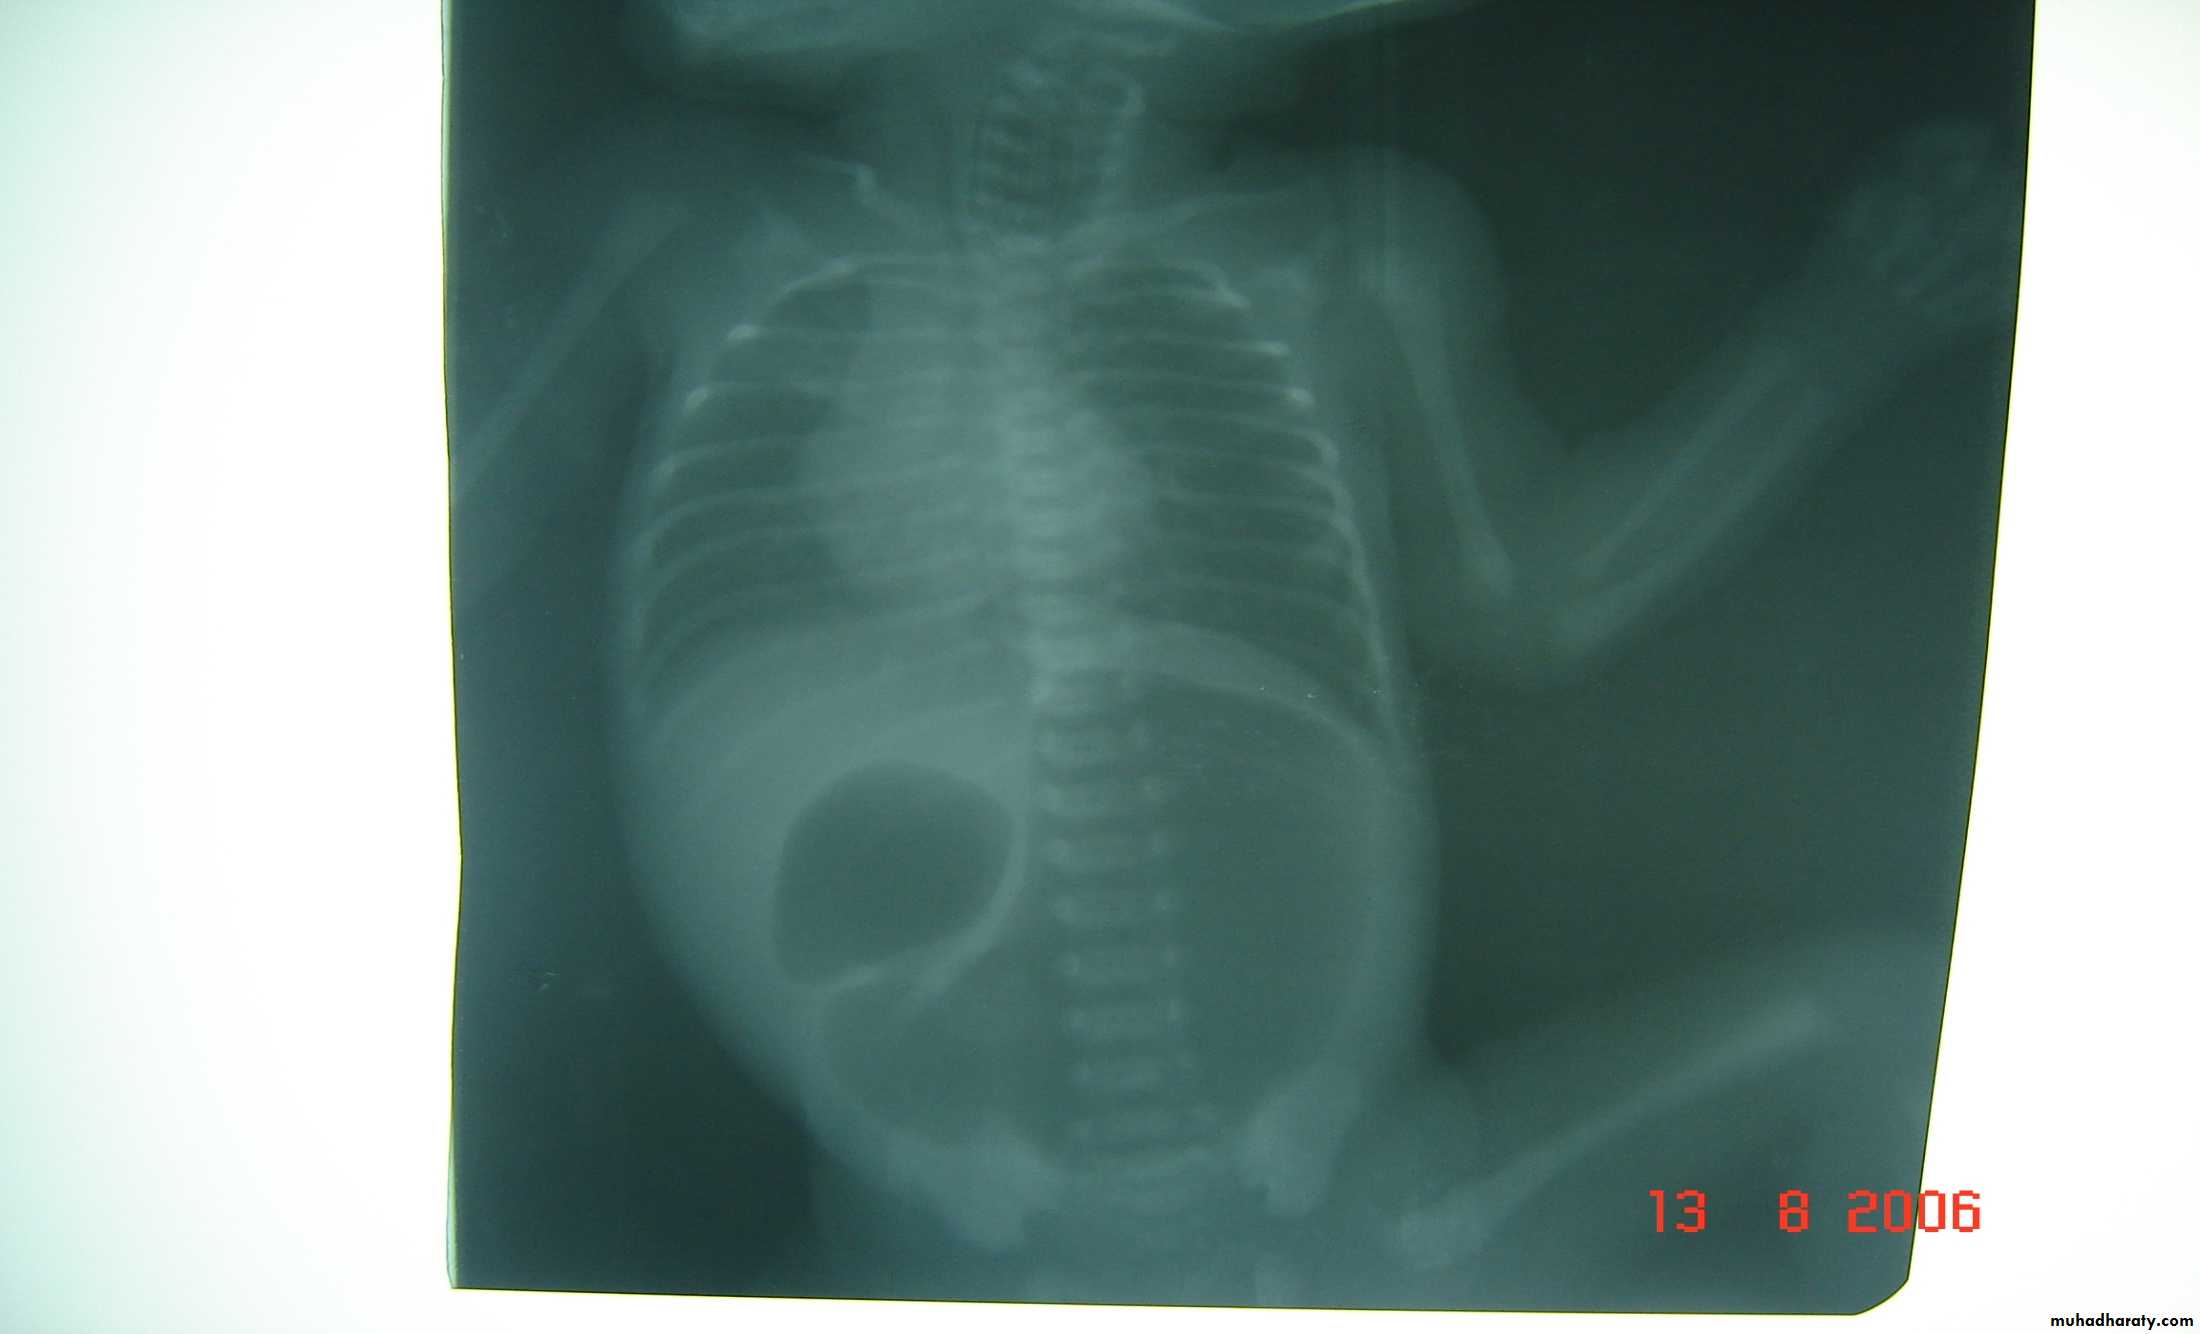

Bowel Obstruction

first photo upper bowel obstruction // second photo lower bowel obstructionDescription:

double bubble signCauses of obstruction in the first photo:

1- duodenal obstruction2- duodenal atrasia

3- annular pancreas

4- mal-roation of bowel

Cardinal symptoms of bowel obstruction (first photo):

1- mild abdominal distention (epigastric distention)2- failure if pass of meconium

3- bile stain vomiting

In pediatric we cannot say small or large bowel obstruction but we say upper

or lower bowel obstruction